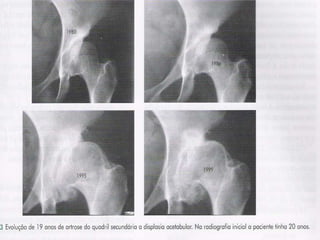

Kellgren e Lawrence

(1957)• Grau 0: normal

• Grau 1: possível estreitamento do espaço

articular medialmente, e possíveis osteófitos

em torno da cabeça femoral

• Grau 2: definido estreitamento articular,

osteófitos pequenos, esclerose, cistos e

deformidades ósseas no fêmur e acetábulo

• Grau 4: visível perda do espaço articular

acompanhada de importante esclerose e

cistos, significativa deformidade da cabeça

femoral e do acetábulo e presença de

grandes osteófitos

Kellgren e Lawrence (1957)•Grau 0: normal • Grau 1: possível estreitamento do espaço articular medialmente, e possíveis osteófitos em torno da cabeça femoral • Grau 2: definido estreitamento articular, osteófitos pequenos, esclerose, cistos e deformidades ósseas no fêmur e acetábulo • Grau 4: visível perda do espaço articular acompanhada de importante esclerose e cistos, significativa deformidade da cabeça femoral e do acetábulo e presença de grandes osteófitos